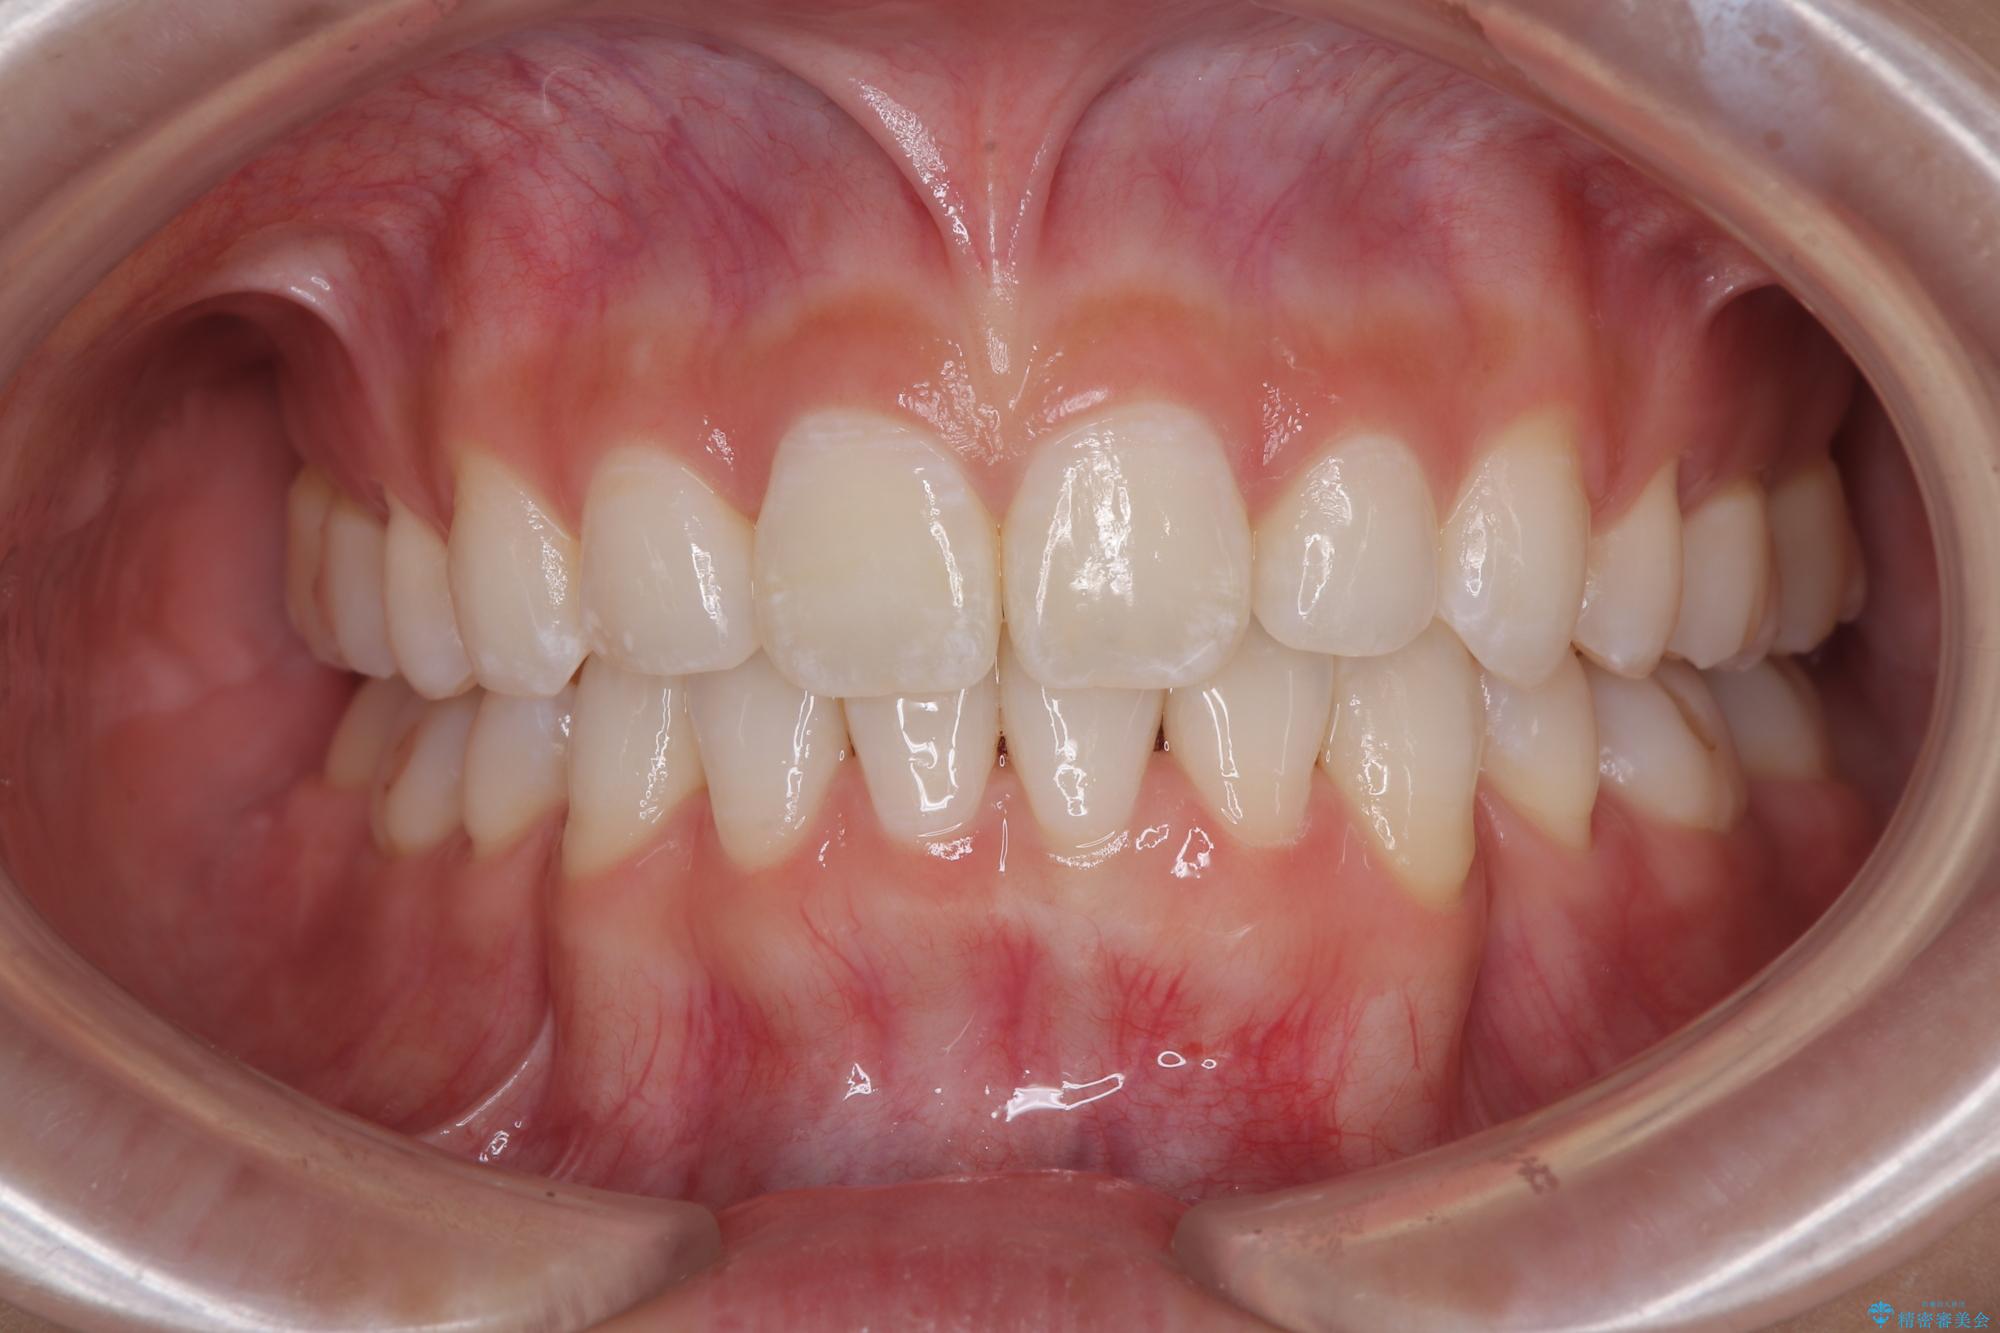

下唇に前歯が当たって跡が残ってしまう状態でしたが、スッキリとした口元に仕上げることができました。

- 2年

- 10-30回